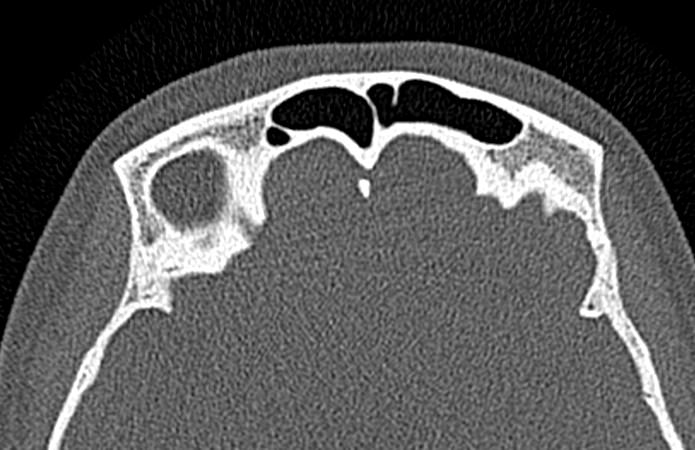

Золотым стандартом в диагностике патологических процессов пазух носа является мультиспиральная компьютерная томография, которая является быстрым безболезненным и неинвазивным (то есть без вмешательства в организм) способом исследования состояния синусов. Метод основан на проникающей способности ионизирующего излучения и получения изображений органов и тканей организма за счет разной степени поглощения ими рентгеновских лучей.

На основе полученных данных цифровые приложения томографов создают трехмерные реконструкции пазух носа, что позволяет оценить пространственное взаимоотношение анатомических структур и помогает в диагностике патологии околоносовых пазух.

Мультиспиральная компьютерная томография дает информацию о состоянии полости носа, носовой перегородки, степени воздушности околоносовых пазух, путей дренирования синусов, состоянии слезных каналов. Сканирование позволяет оценить толщину слизистой, наличие патологического содержимого в просвете пазух (уровня «жидкости»), выявить опухолевые образования. С помощью КТ можно провести точную диагностику травматических повреждений костей лицевого черепа, определить локализацию инородных тел, попавших в полости синусов.

С помощью объемной реконструкции можно перед оперативным вмешательством увидеть особенности анатомии ЛОР-органов, определить точное расположение патологического очага по отношению к окружающим тканям. Компьютерная томография помогает в диагностике аномалий развития придаточных пазух носа, слезоотводящих каналов.